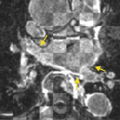

Here registration of the pulmonary veins was attempted using fiducially placed on consistent landmarks on the PVs, yet far from the LA (i.e. in the lungs). Again, misregistration of the PVs was observed.